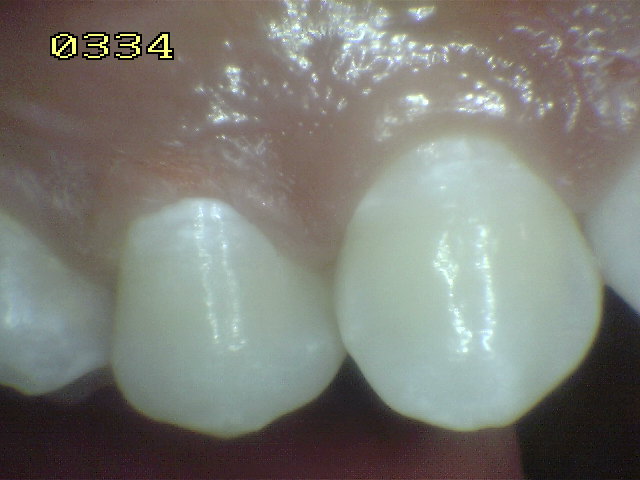

Casos clínicos de

fluorosis leve. |

Se caracteriza por esmalte normal,

liso, traslucido y cristalino de color uniforme.

Estas características permanecen aún después

del secado con aire prolongado |

Las manchas opacas por fluorosis leve deben

diferenciarse con los códigos1 y 2 de ICDAS. En las

fluorosis el esmalte aparece brillante; mientras que

en el proceso de caries se observa un blanco aspecto

de tiza. (sin brillo) |